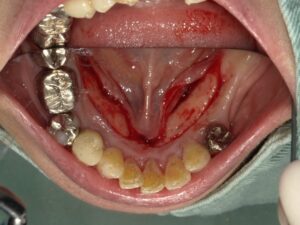

コーヌスデンチャーとは残っている歯に冠のような金属を被せてその上にさらに金属を被せる

2重の冠でできた入れ歯になります。茶筒の原理で固定されるため安定感が高く、審美性や装着感に

優れています。ドイツで開発されたテレスコープデンチャーの一種です。

画像の様なイメージになります。針金を使いませんので

見た目がよくまた維持力も大きくとても良好な義歯となります。

取り外しの動画は下記になります。しっかりと装着されています。